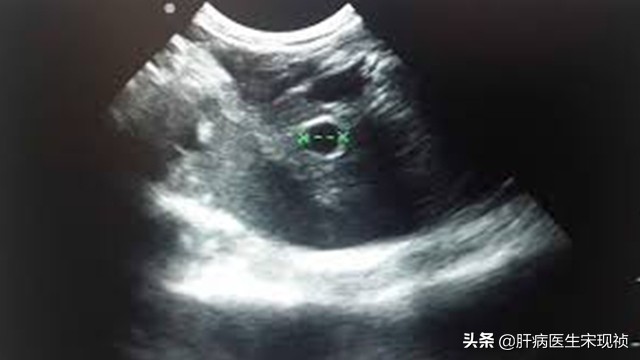

正常的肝脏内部回声是由一些分布均匀、大小相似和辉度相近的细小的光点组合成的。如果肝脏有损伤,那么肝内回声就会根据损伤的程度进展而有所变换,如增粗、增强,肝、肾的回声反差也会增大。结缔组织增生明显者,肝实质内可见弥漫性散在的线状回声,有时可见小结节回声。这些变化在慢性肝炎和肝硬化都可能会出现。

回声增粗、增强,可见斑块状强回声区,用适宜的增益条件扫描,看见多数低回声小结节镶嵌在肝实质内,前者由纤维化所致,后者系再生结节;随病变发展,出现肝结构紊乱、肝实质不均质改变,需要与弥漫性肝癌的声像图相鉴别。

肝实质回声增粗属于B超影像的专用术语,提示有肝功能异常可能。诊断为肝硬化还需要结合其他临床表现以及检查结果判断,例如:脾脏大小、腹水、肝功能检查等等。